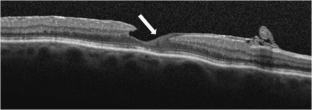

Thirty-five patients were included. At baseline, six fellow eyes (17%) showed a normal foveal profile, 26 (74%) had a tractional ERM, and three cases (9%) revealed a bilateral LMH, one of them with a lamellar hole-associated epiretinal proliferation (LHEP). A posterior vitreous detachment (PVD) was present in 29 patients (83%), four (11%) had only a vitreo-papillary adhesion (VPA), and two (6%) had both vitreo-macular adhesion (VMA) and VPA. After a mean follow-up of 4.6 ± 1.9 years, one eye (3%) developed a vitreous detachment from the macula with persistent VPA, and one developed a PVD from a VPA with subsequent ERM formation.

BCVA and mean CFT remained stable in 35 eyes (100%). Likewise, no B-FAF signal variations were detected. One patient developed a LMH during the 3rd year of follow-up.

Fig. 2